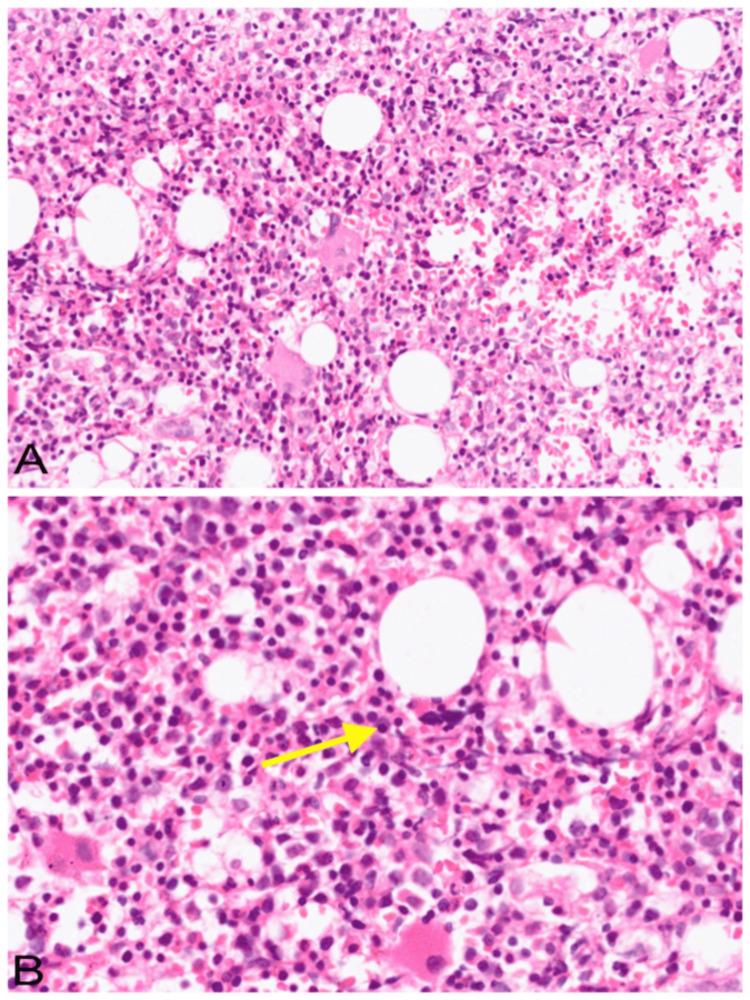

Multiple myeloma (MM) is a complex haematological malignancy characterized by the clonal proliferation of plasma cells within the bone marrow. It is the second most common haematological malignancy that presents in elderly patients. The integration of complementary medicine into conventional cancer care is increasingly observed among patients, driven by factors such as symptom management, holistic well-being, and cultural alignment. This case report presents the integrated management of a 65-year-old male patient diagnosed with MM, who received both chemotherapy and Siddha medicine to alleviate constitutional symptoms and improve overall well-being. The patient complained of weakness, easy fatigability, and insomnia. The diagnosis of MM was established elsewhere through serum protein electrophoresis, immunofixation, and bone marrow biopsy. He was treated with the bortezomib, lenalidomide, and dexamethasone (BLD) regimen along with a combination of Siddha herbal and herbo-mineral formulations. After six months, the patient demonstrated significant improvements in haematological parameters, general physical condition, and quality of life. This case highlights the potential benefits of integrating traditional Siddha medicine with conventional allopathic therapy in managing MM.

多发性骨髓瘤(MM)是一种复杂的血液系统恶性肿瘤,其特征为骨髓内浆细胞的克隆性增殖。它是老年患者中第二常见的血液系统恶性肿瘤。在症状管理、整体健康状况和文化契合等因素的推动下,患者越来越多地将补充医学纳入传统癌症治疗中。本病例报告介绍了一名65岁男性MM患者的综合治疗情况,该患者接受了化疗和悉达医学治疗,以缓解全身症状并改善整体健康状况。患者主诉乏力、易疲劳和失眠。MM的诊断在其他地方通过血清蛋白电泳、免疫固定和骨髓活检得以确立。他接受了硼替佐米、来那度胺和地塞米松(BLD)方案治疗,同时还服用了悉达草药和草药-矿物质配方组合。六个月后,患者的血液学参数、一般身体状况和生活质量有了显著改善。本病例突出了在MM治疗中整合传统悉达医学与传统西医治疗的潜在益处。